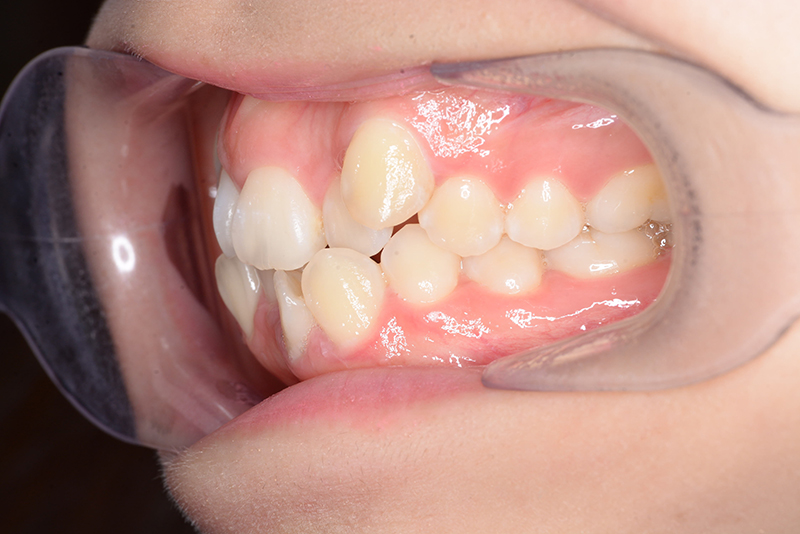

| 口腔内所見 | over jet 4.5mm、over bite 4.0mm、大臼歯関係 I級で上下顎前歯部に叢生が認められた。 |

| 批評・予后 | 叢生が大きかった影響もあり、治療期間は20ヶ月と比較的短い期間が終了できた。治療後においては口元の改善、咬合の緊密化は達成できたように思う。 |